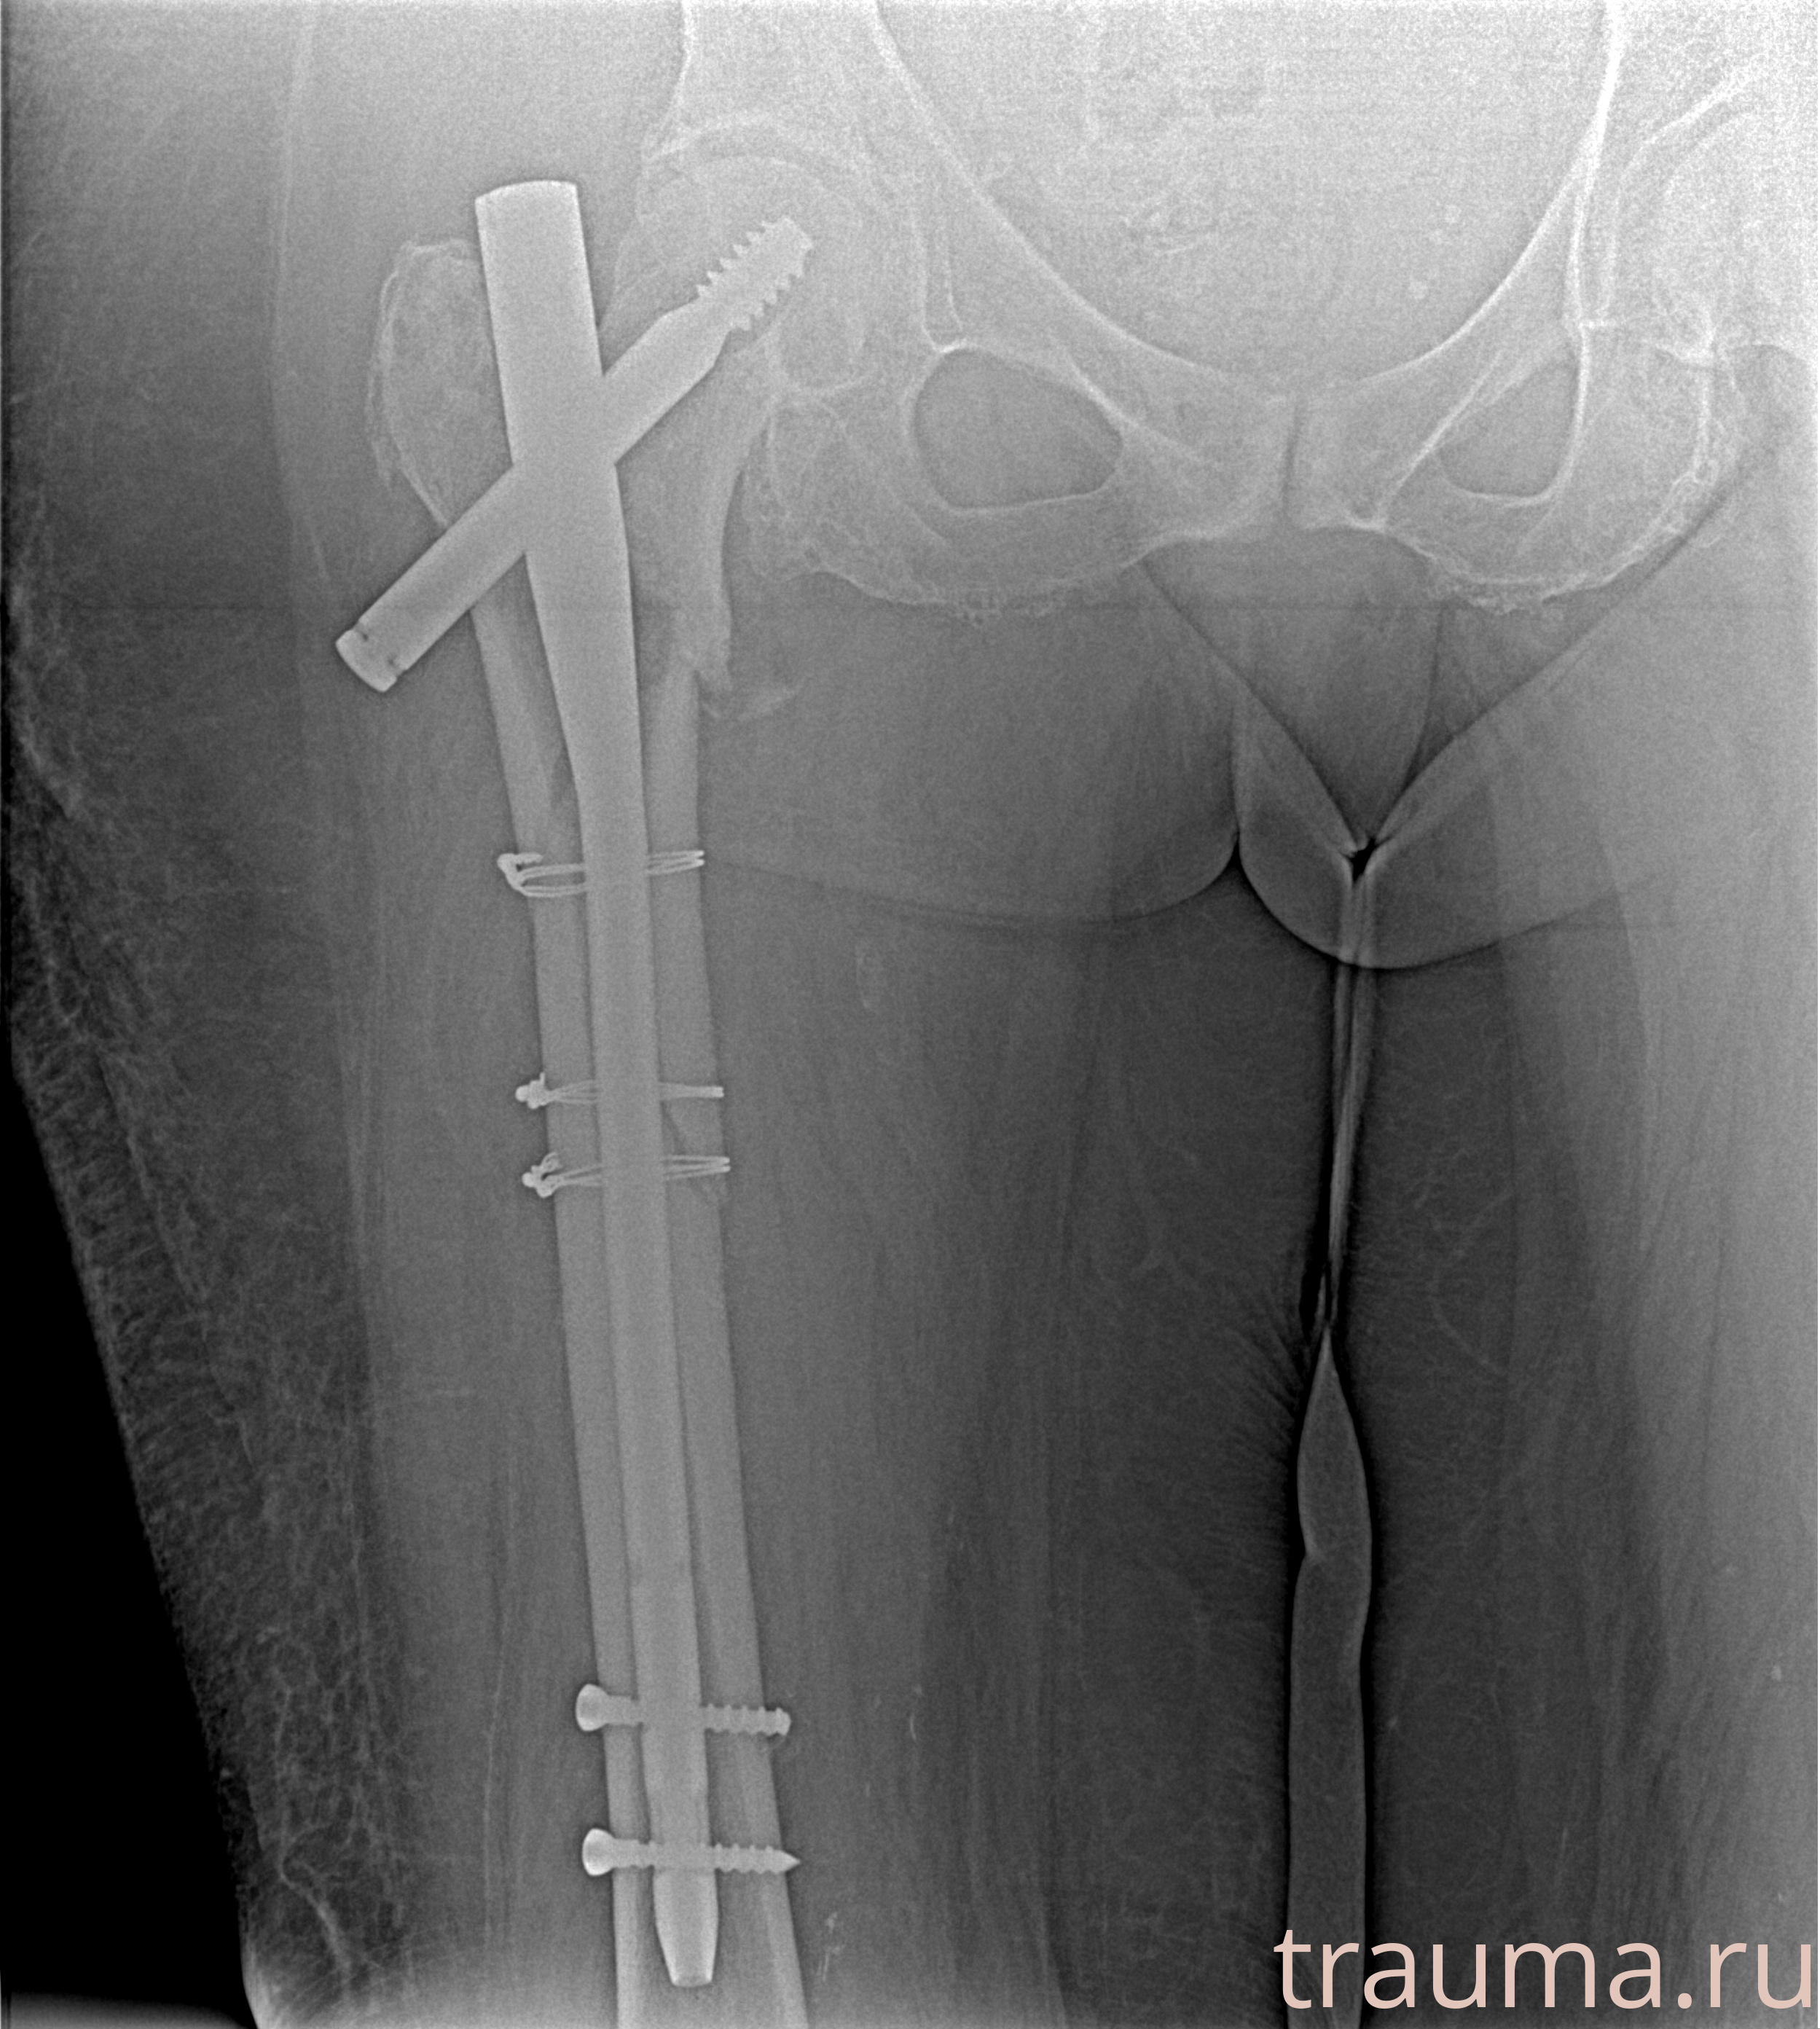

Рентгенограммы

Рентген на дому: по вашему адресу приезжает врач-рентгенолог, травматолог-ортопед с мобильным рентгеновским аппаратом, проводит диагностику травмы или заболевания, делает необходимые рентгенограммы, дает рекомендации по дальнейшему лечению. Получить качественные снимки в домашних условиях возможно благодаря уникальной методике, разработанной МосРентген Центром для института  Склифосовского